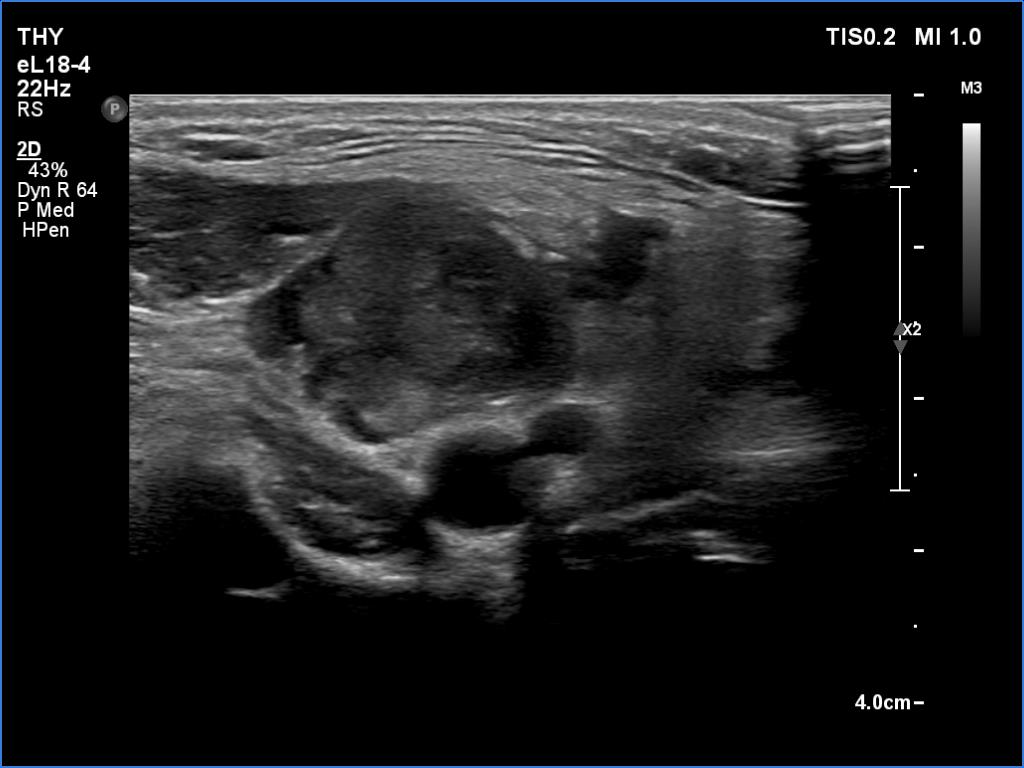

Ultrasonography. The thyroid was hypoechoic. The right lobe had a heterogeneous, dominantly minimally/moderately hypoechoic nodule in the ventrolateral part which had irregular borders and both perinodular and intranodular vascularity. There was another, hyperechoic star-like lesion in the central part of the right lobe. This lesion presented microcalcifications and was avascular. The left lobe was homogeneously hypoechoic.